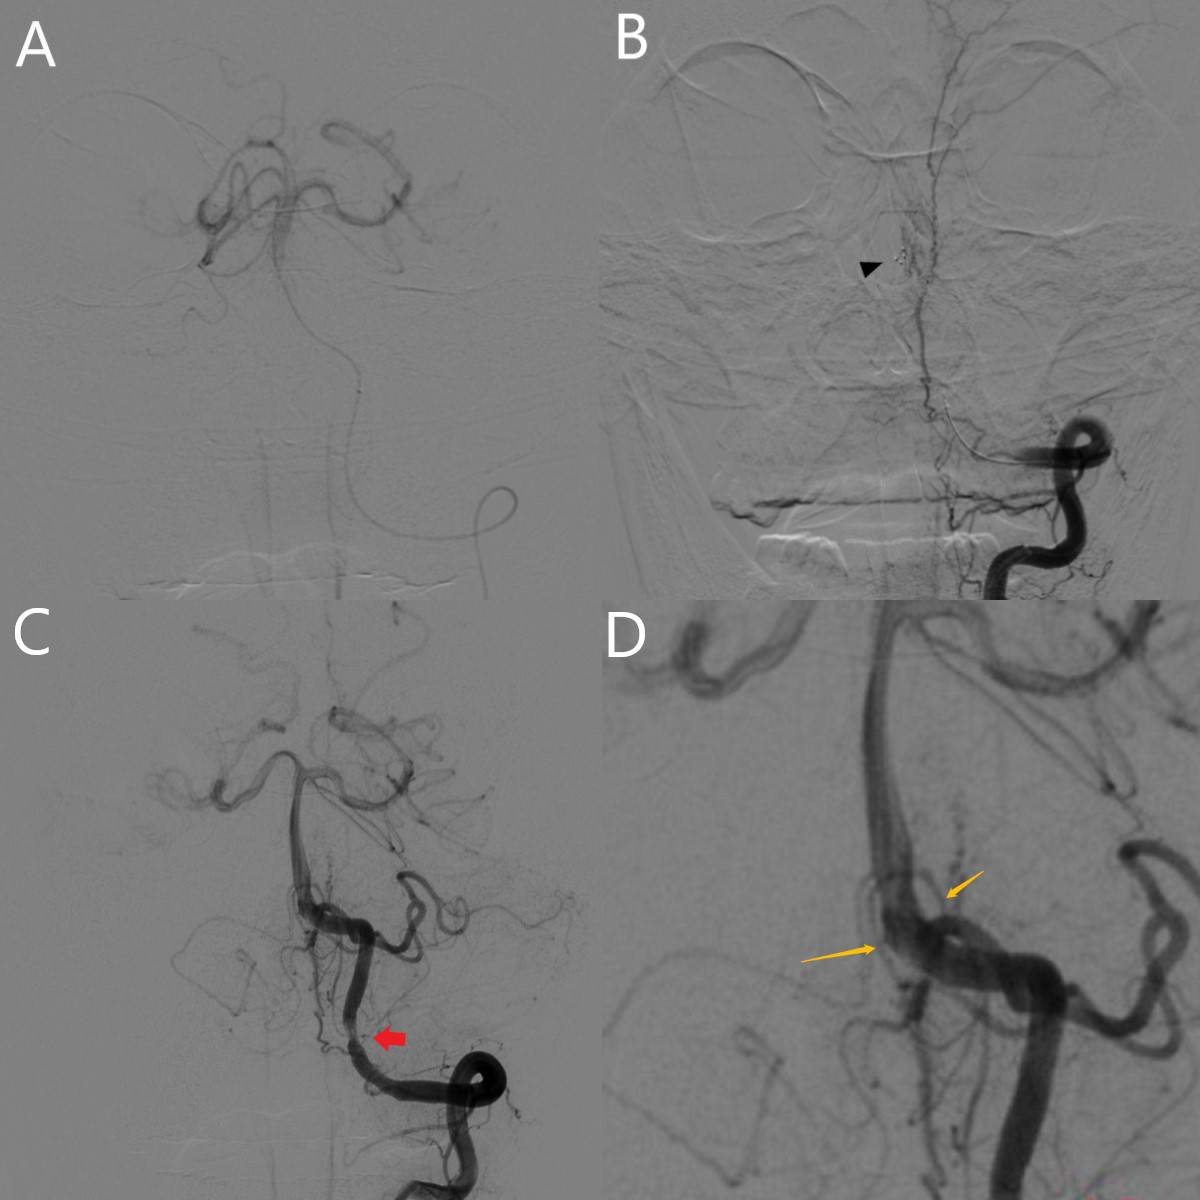

患者平卧DSA床,局麻成功后,用碘伏常规消毒手术区皮肤,铺无菌巾单。取右侧股动脉为穿刺点,Seldinger法穿刺成功后置入25cm 6F鞘。行经皮选择性脑血管造影见左侧椎动脉急性闭塞,左侧小脑后下动脉无显影,左侧小脑前下动脉由右侧椎动脉反流代偿,右侧椎动脉通畅,并且未见脊髓前动脉发出,基底动脉,双侧大脑后动脉等重要分支通畅(图2)。0.035in的泥鳅导丝导引下将6F导引导管超选至左侧椎动脉V2-V3段。路图下使用Rebar18微导管在Synchro微导丝带领下进入基底动脉。手推造影确认流出道后,释放一枚Solitaire FR支架(6*30mm),负压下抽拉支架1次后,造影见左侧椎动脉再通,另见左侧椎动脉V4段中重度狭窄,脊髓前动脉双支由左侧椎动脉发出,远端流速TICI3级(图3)。等待10分钟后造影复查提示血流明显减慢,遂予以鲁南恒康团注8ml,微泵静推6ml/小时维持10分钟后造影复查,见血流速度恢复至TICI3级。遂结束手术,缝合器闭合穿刺部位。

图3. A:微导管到位手推造影确认流出道;B:支架释放(▲支架远端Marker);C:使用负压抽吸下支架取栓一次后血流恢复,可见左侧椎动脉V4段近端一处粥样硬化狭窄(↑所指),脊髓前动脉,左侧小脑前下动脉及后下动脉显影;D:图像放大后可见脊髓前动脉两支均起源于左侧椎动脉。